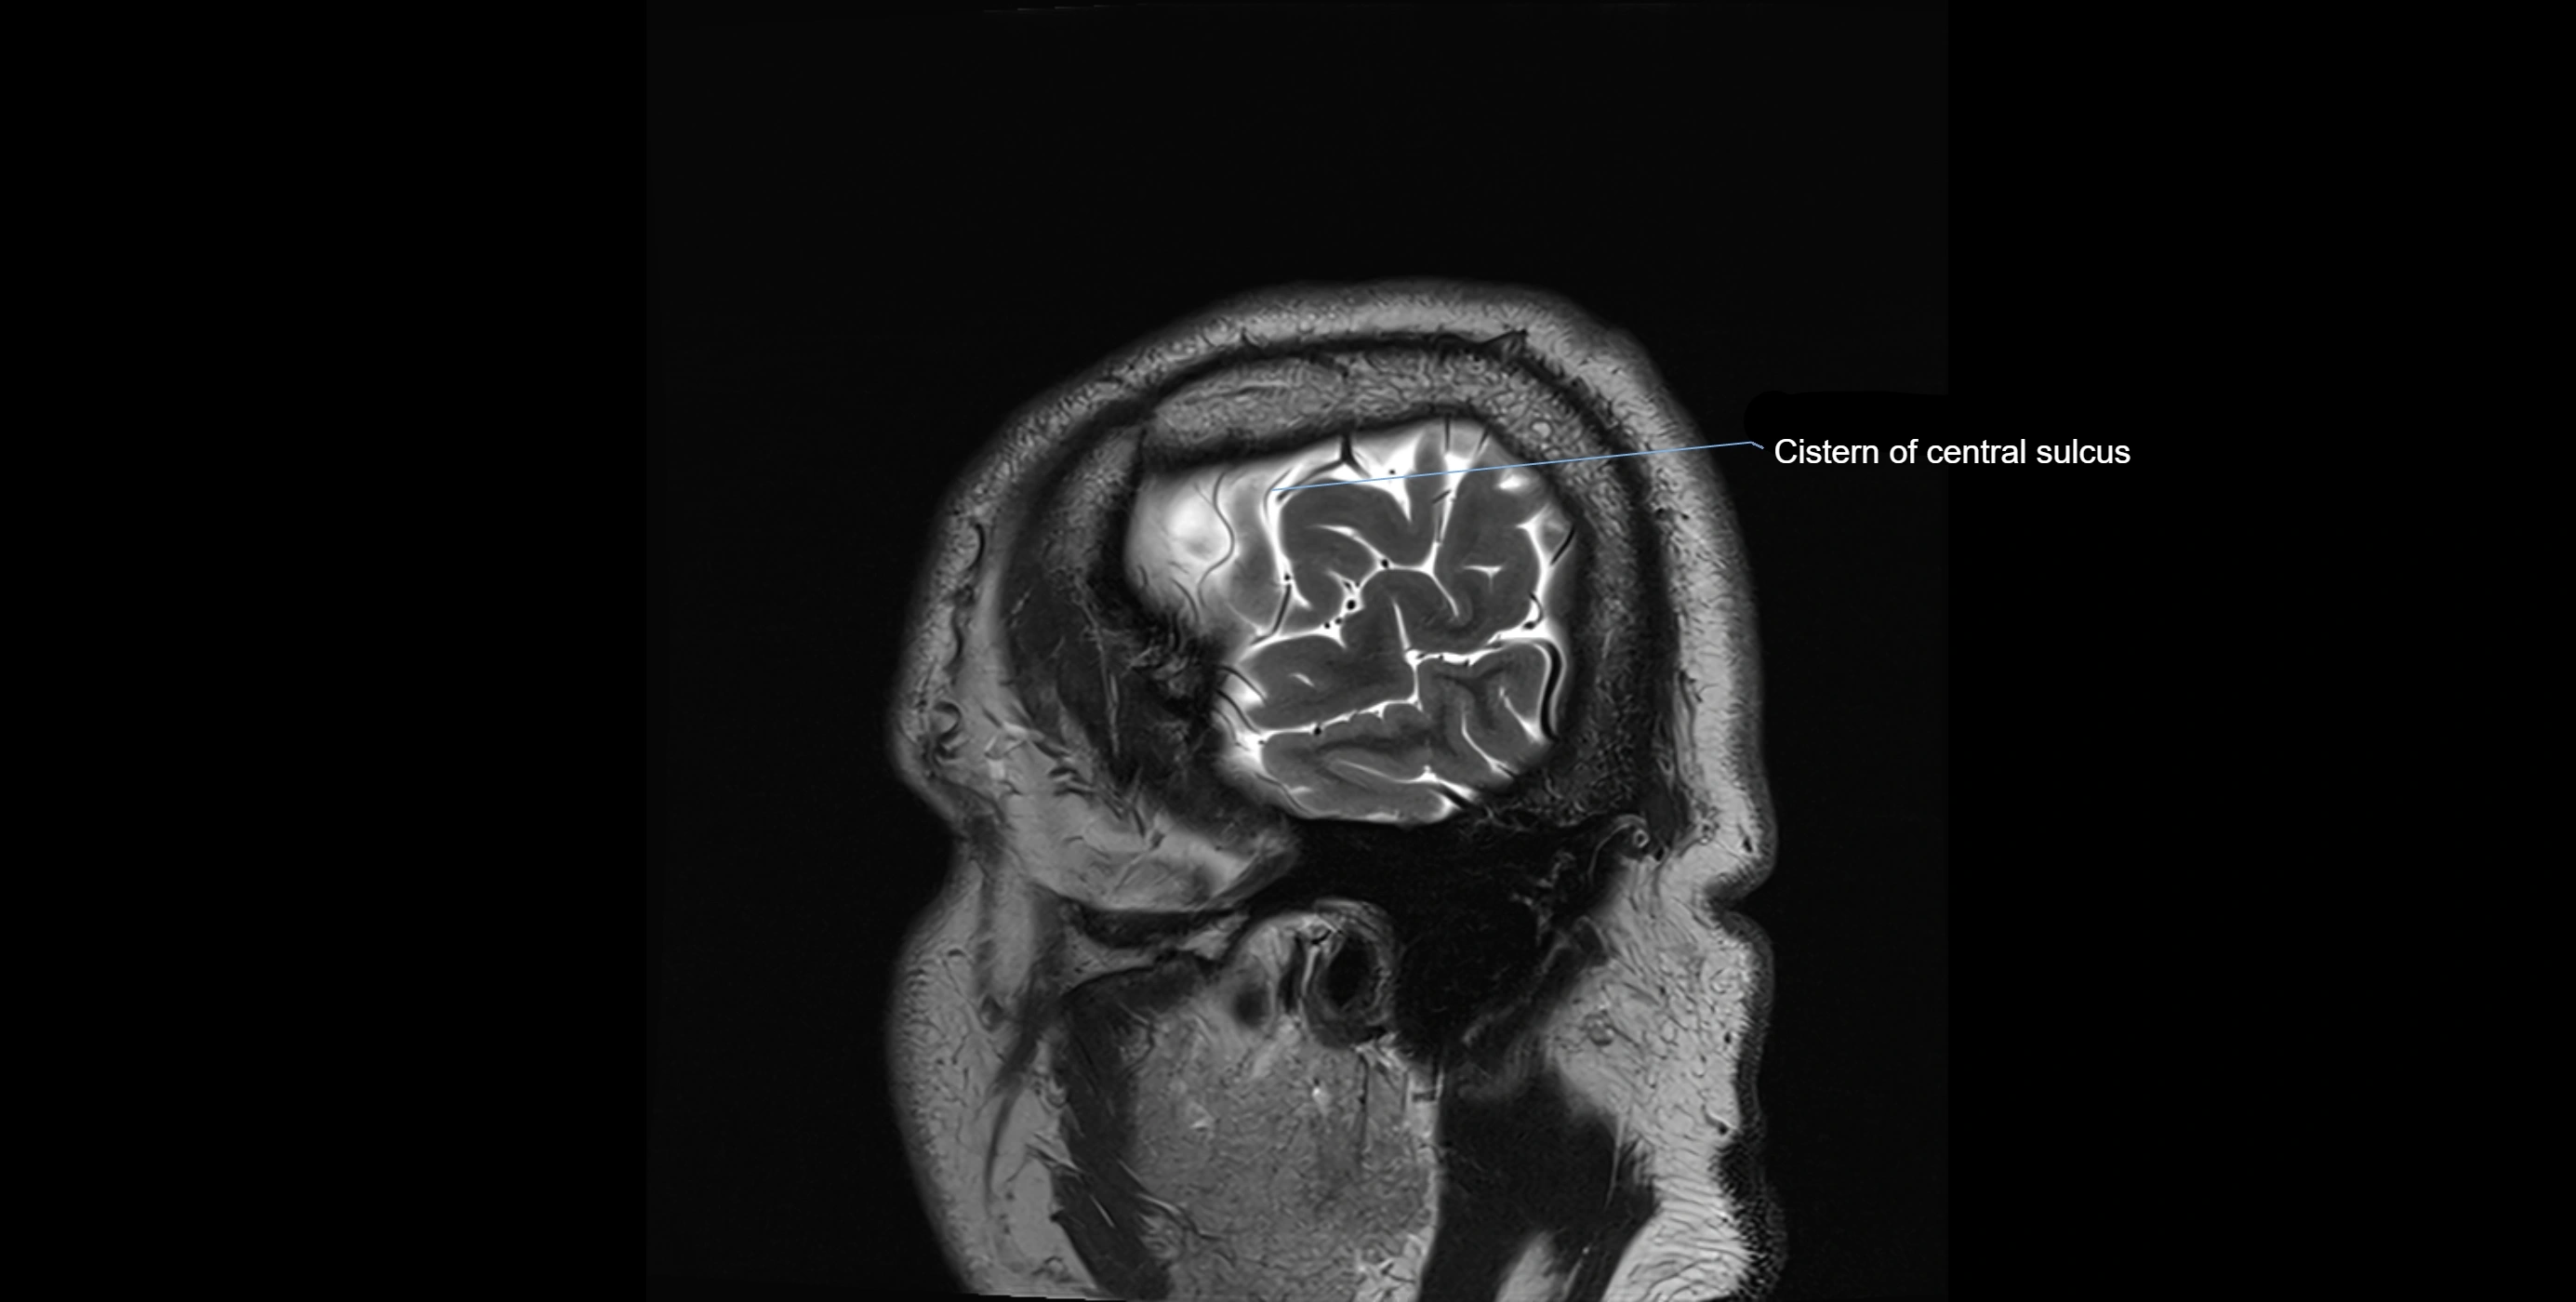

MRI images

image